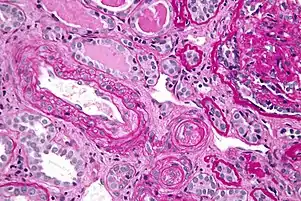

The most important clinical complication of scleroderma involving the kidney is scleroderma renal crisis (SRC), the symptoms of which are malignant hypertension (high blood pressure with evidence of acute organ damage), hyperreninemia (high renin levels), azotemia (kidney failure with accumulation of waste products in the blood), and microangiopathic hemolytic anemia (destruction of red blood cells).[14] Apart from the high blood pressure, hematuria (blood in the urine) and proteinuria (protein loss in the urine) may be indicative of SRC.[15]

Scleroderma renal crisis (SRC) is a life-threatening complication of systemic sclerosis that may be the initial manifestation of the disease. Renal vascular injury (due in part to collagen deposition) leads to renal ischemia, which results in activation of the renin-angiotensin-aldosterone system (RAAS). This raises blood pressure and further damages the renal vasculature, causing a vicious cycle of worsening hypertension and renal dysfunction (e.g., elevated creatinine, edema). Hypertensive emergency with end-organ dysfunction (e.g., encephalopathy, retinal hemorrhage) is common. Thrombocytopenia and microangiopathic hemolytic anemia can be seen. Urinalysis is usually normal but may show mild proteinuria, as in this patient; casts are unexpected.